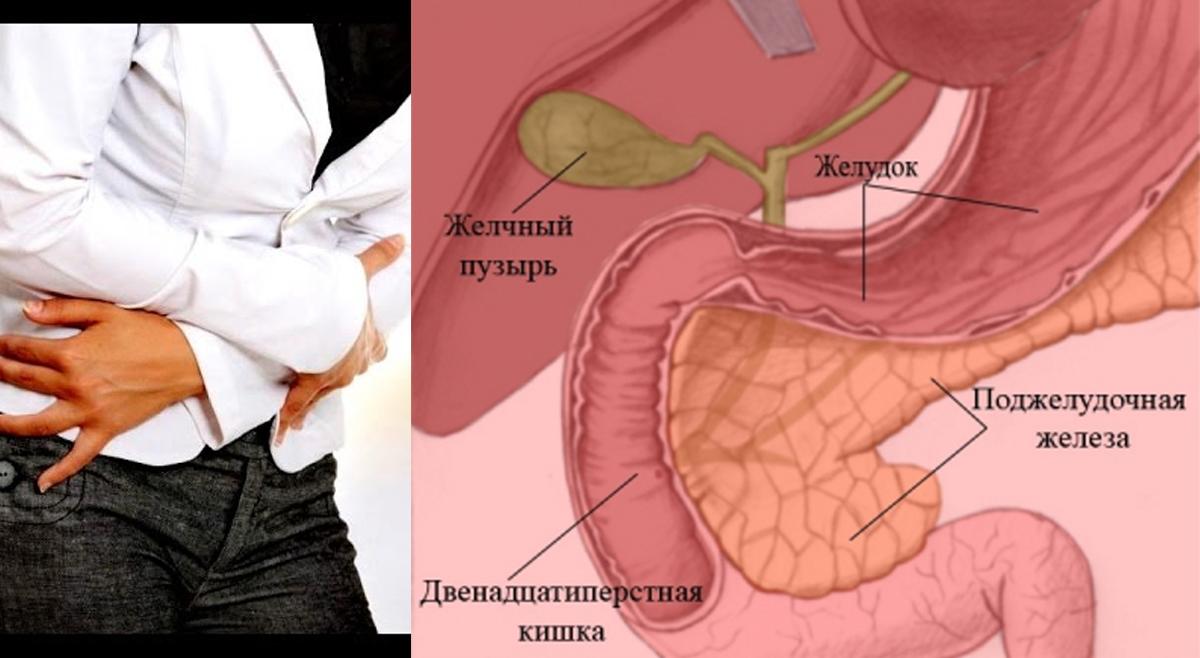

Анатомическое расположение поджелудочной железы

ПЖ располагается в брюшной полости, ближе к I–II позвонкам поясничного отдела позвоночника. Орган плотно крепится на задней стенке желудка, а 12-перстная кишка окружает ее, поддерживая в необходимом положении.

По анатомическому строению орган делится на 3 составных части: это головка, тело и хвост. Головкой ПЖ обращена к желчному протоку, тело находится за желудком, ближе к его нижней части. Рядом с телом в норме располагается поперечно-ободочная кишка. Хвостом ПЖ обращена к селезенке, и уходит к левому подреберью. По отношению к пупку, со стороны брюшной стенки, ПЖ расположена над ним, на 5-10 см выше.